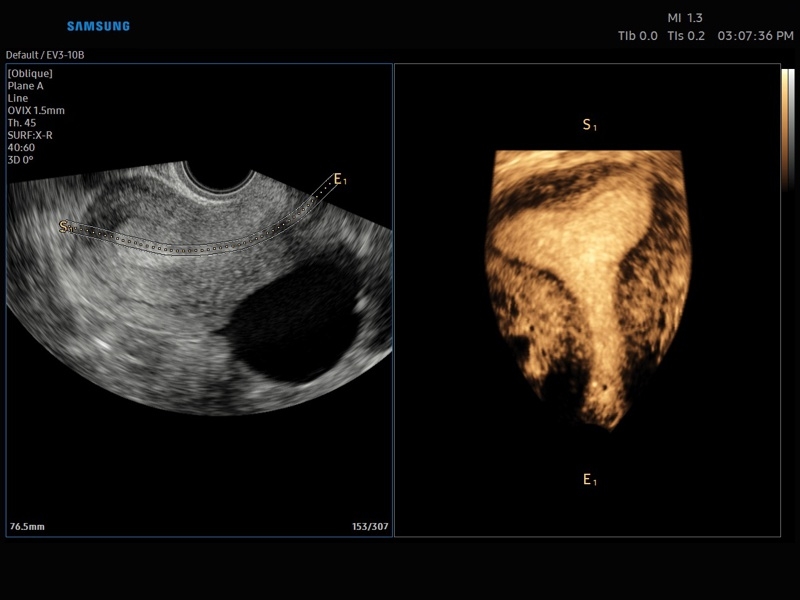

• Smart 4D с технологиями Realistic VUE и Crystal VUE

• 3D - трехмерное сканирование объемными датчиками в статическом режиме в серой шкале и восстановление объемной структуры сосудов в режиме цветного / энергетического допплера (необходим Static 3D).

• 4D - трехмерное сканирование объемными датчиками в реальном масштабе времени (необходима опция Smart 4D).

• Модуль Realistic Vue - программа реконструкции реалистичного 3D УЗИ, при котором на объемное изображение накладывается виртуальный источник освещения. Специальный процессинговый алгоритм воспроизводит трехмерную анатомию плода с исключительной детализацией.

• МодульCrystal Vue- программа реконструкции прозрачного 3D УЗИ, которое получается при одновременном усилении внутренних и наружных структур. Применяется для визуальной оценки состояния плода и матки, помогает лучше идентифицировать мягкие ткани и кости.

• Система Static 3D - трехмерное сканирование объемными датчиками в статическом режиме в серой шкале и восстановление объемной структуры сосудов в режиме цветного / энергетического допплера).

• СистемаLive 3D- трехмерное сканирование объемными датчиками в реальном масштабе времени (4D).

• OVIX(Oblique View eXtended) - получение фрагмента трехмерного изображения (в виде нескольких полупрозрачных сканов, последовательно наложенных один на другой) в направлении произвольного косого среза трехмерного объекта исследования.